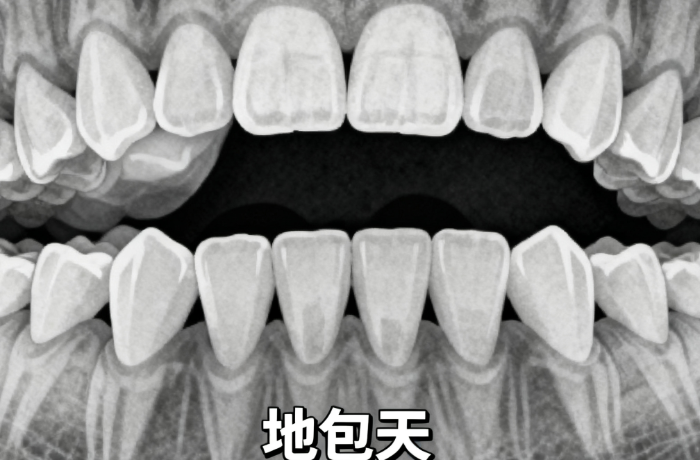

适合人群:3-12岁儿童,有地包天、龅牙等问题